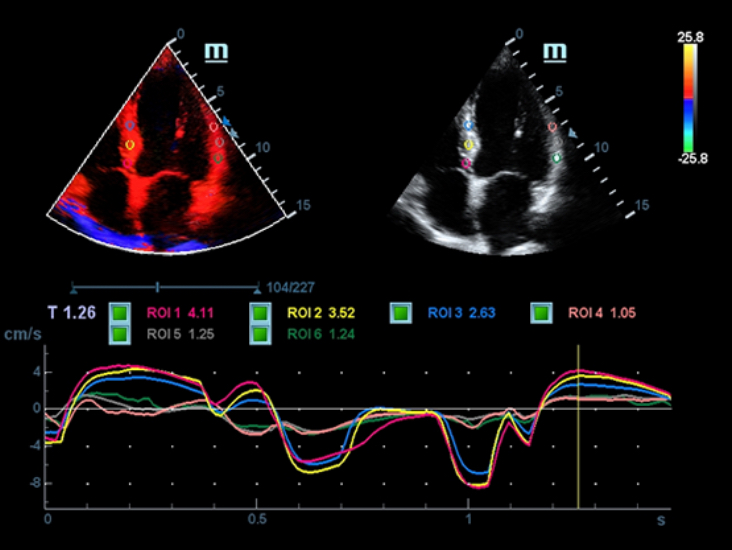

-Auto EF

Auto EF is an intelligent way to analyze 2D echo clips to automatically recognize diastole & systole frames and output a series of measurements to evaluate left ventricle function for more productivity, such as EDV/ESV/EF.